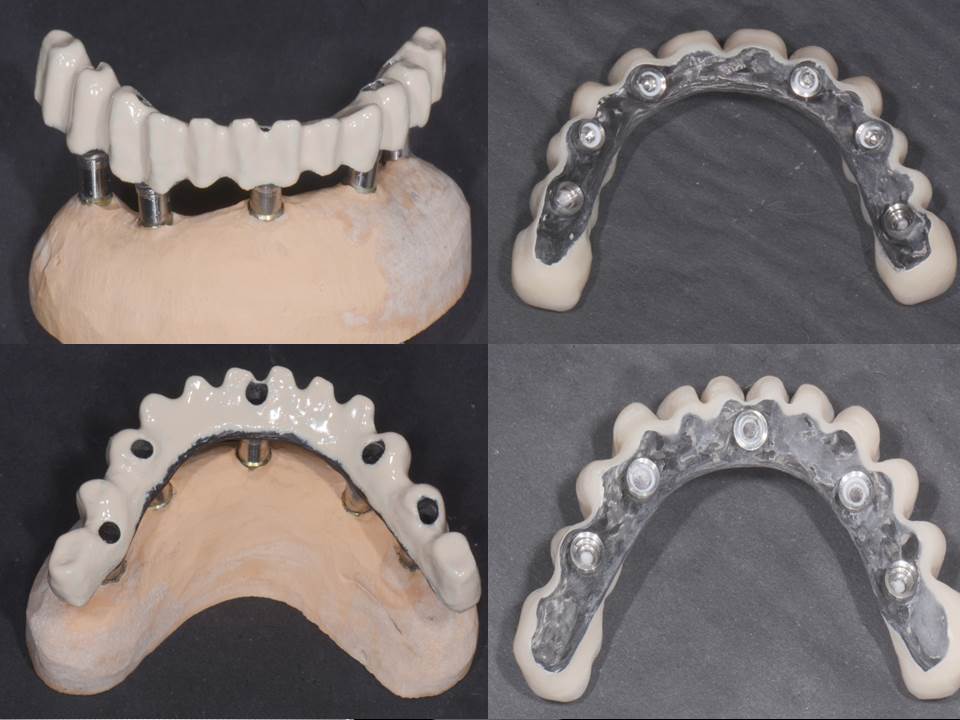

Prótesis fija OT BRIDGE

E - BOOK y CASOS CLÍNICOS

CASOS CLÍNICOS